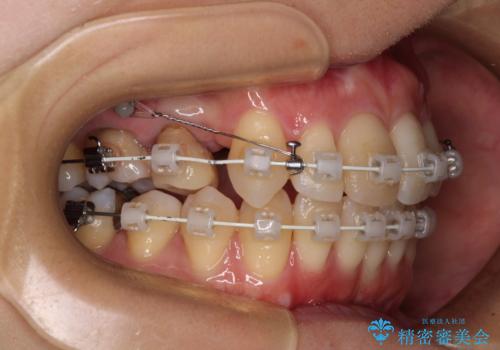

- 矯正装置

- 審美装置

上顎左右第一小臼歯を抜去して、ワイヤー装置にて口元の突出感を改善するよう矯正治療を行うこととしました。